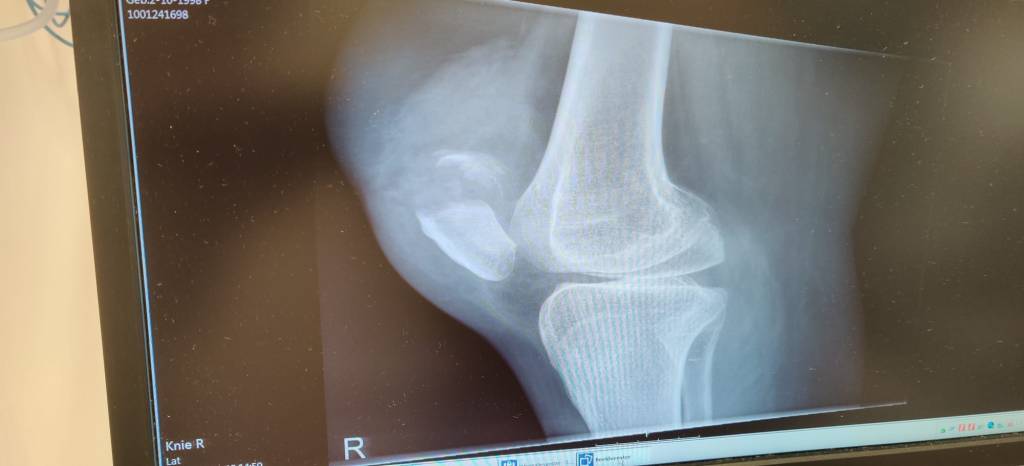

Daar lag ik dan, in het ziekenhuis, op de spoedeisende hulp. Mijn ervaring met de spoedeisende hulp is nooit echt goed geweest. Het is altijd ontzettend lang wachten, ondertussen hoor en zie je allemaal mensen weggaan en weer binnenkomen die voorrang hebben en ik krijg vaak het gevoel dat ze je een beetje vergeten. Maar dat was niet zo in het ziekenhuis in Apeldoorn. Ik werd ontzettend snel geholpen en het personeel was daar zo lief. Ik mocht bijna direct door voor een foto, en dat was ook de eerste keer dat ik naar mijn knie keek. Nou het was alsof er een voetbal onder mijn huid was gekropen, zo dik was het. Ik wist bij de ligging van mijn been, toen ik viel, dat het niet goed zat. Maar toen ik mijn knie ook echt zag barstte ik in janken uit en kon ik niet meer stoppen. Een uur later kreeg ik het nieuws dat mijn knieschijf gebroken is….

Ik, die iets heeft gebroken. Dat is echt nog nooit voorgekomen. En dat terwijl ik echt all the time val. Ik val van trappen, ik val van barkrukken, van mijn scooter, ik val door stoeptegels, ik val over mijn eigen voeten, ik struikel nog net niet over de lucht. In al die jaren heb ik nooit iets gebroken en nu ineens wel. De onzekerheid kwam aanzetten. Want ik heb toch echt een spierziekte.. Ik hoor vaker verhalen over dat mensen met een spierziekte die wat hebben gebroken, nooit meer de functie terugkrijgen die ze hadden. Als je mij een beetje kent. Weetje dat mijn benen echt mijn alles zijn. Duhh voor iedereen, maar voor mij waren ze nog net iets bijzonderder omdat ik ondanks mijn handicap, door die benen (soort van bijna) alles kon. Wat ik nog het aller apartste vond, was dat mijn knie de 2 dagen voor het ongeluk al hartstikke pijn deed, en ik in de ochtend wakker werd met de gedachten dat ik mijn been brak.

Als je je knieschijf hebt gebroken, moet je bijna altijd een operatie ondergaan. Maar bij mij twijfelde ze of dat wel verstandig was i.v.m. mijn handicap. Uiteindelijk zou een specialist in Groningen met mij contact opnemen en ik moest tot die tijd maar naar huis. zat ik daar dan vier uur later na de gebeurtenis, met een gebroken knieschijf en een brace om mijn been te wachten op de auto van mijn vriend. Om een rit van 2 uur te maken achter in de auto…